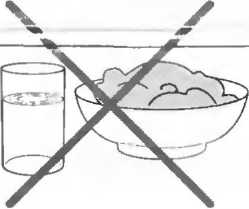

1. Подготовка

Пациент не должен пить и есть в течение 8 ч перед исследованием. Если жидкость необходима для предотвращения дегидратации, можно давать пациенту только воду. При острой симптоматике исследование можно проводить без подготовки. Детям, если позволяют клинические условия, пища и вода не даются в течение 3 ч до исследования.